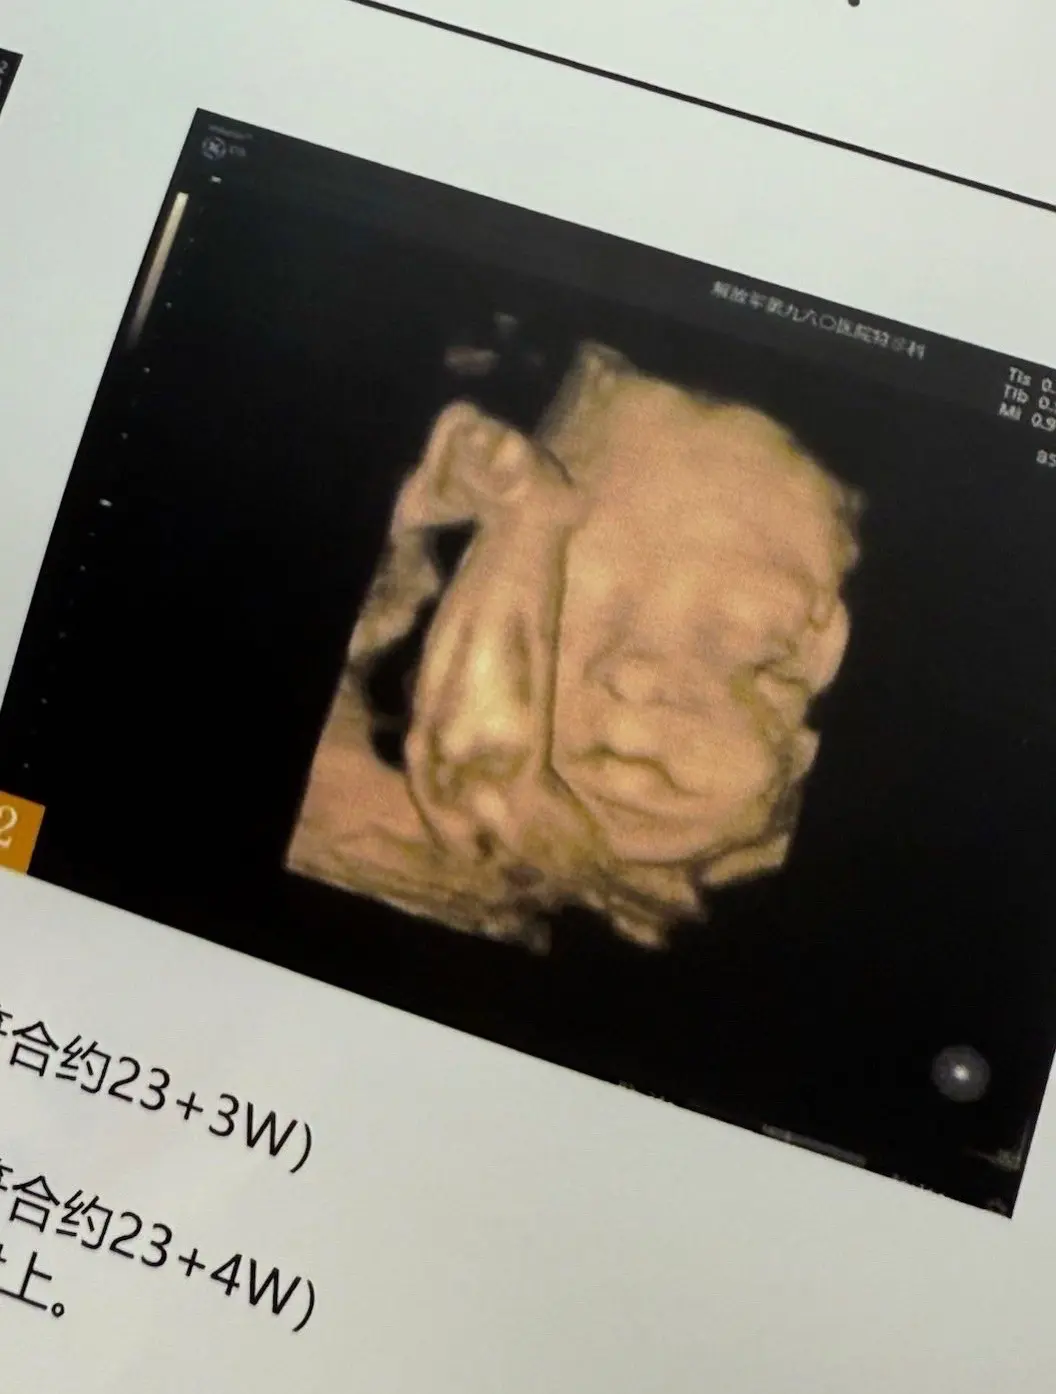

30w|大大的肚子住着一个小小的你👶🏻